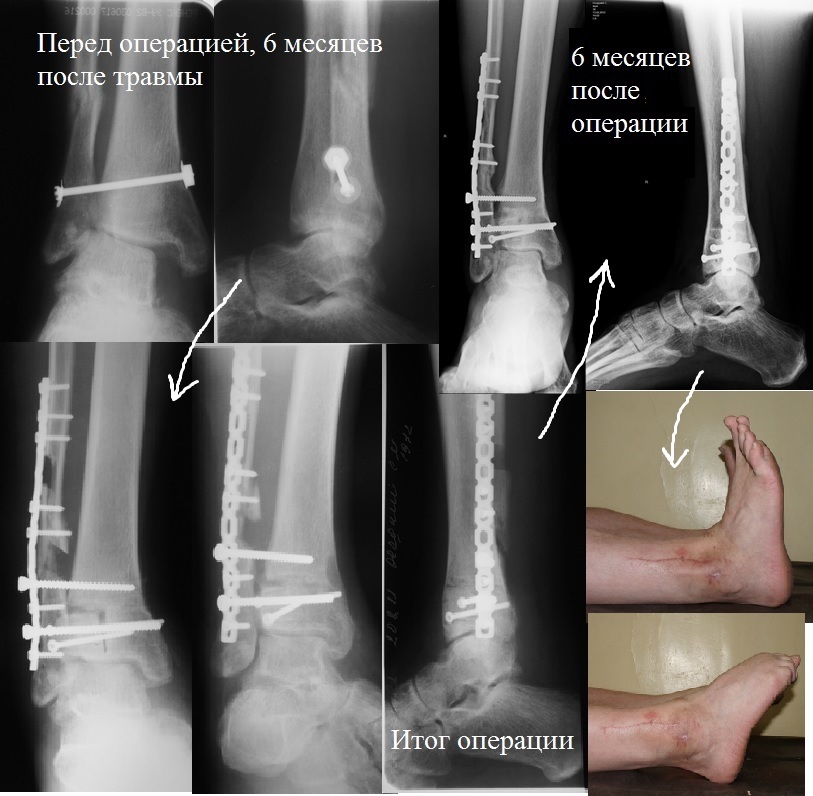

[Ortho] Сросшиеся лодыжки. Артродез или реконструкция?

Ой, простите. Не сразу заметил маршевую латеральную импрессию. Тогда,

конечно, ещё фигурная остеотомия дистального эпиметафиза большеберцовой

кости с устранением вальгуса. Клинический пример в приложении. Сейчас

после операции прошло уже полтора года, пациент на повторные приёмы

перестал ходить, недавно общался с ним по телефону, жалоб нет, вернулся

к прежним занятиям, работа - весь день на ногах, егерь в охотничьем

хозяйстве. Пригласил сделать контрольные снимки, говорит - некогда...